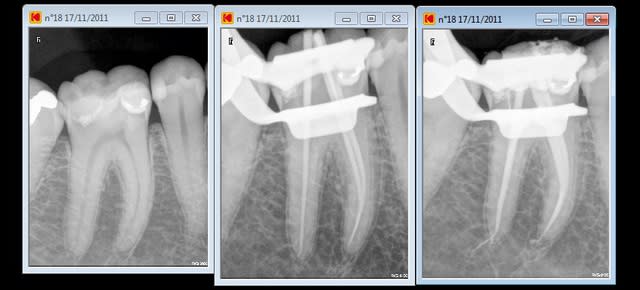

Content de moi.

En fait, c'est la même endo, le radios ont été interverties la finale a été prise sans clamp.... mais l'endo à été faite sous digue.

Tout est évidemment nécrosé, et donc aucune constriction sauf étrangement en D. J'y suis donc allé au sonar électronique.

Aucun symptôme, pas de suintement, faible saignement au bout des cônes de papier dont je suis venu à bout avec 3 ou 4 sachets de 5 cônes.

Maître cône ajusté sur donnée du magnifique localisateur Joypex 5, c'est-à-dire coupé la gutta au bout pour que ça colle à la longueur électronique.

Et thermocompacteur en restant à 5 mm de la LT

Il y a l'air d'y avoir un cône en M (j'aimerais croire que ce n'est que de la pâte), peut-être aurais-je dû donner un coup de finger spreader avant pour bien écraser et mouler le cône.

Et une compression au fouloir à amalgame de gutta sur le plancher pour compresser de la pâte sur des canaux accessoires du plancher, ici apparemment absents.

Temporisation à l'IRM.